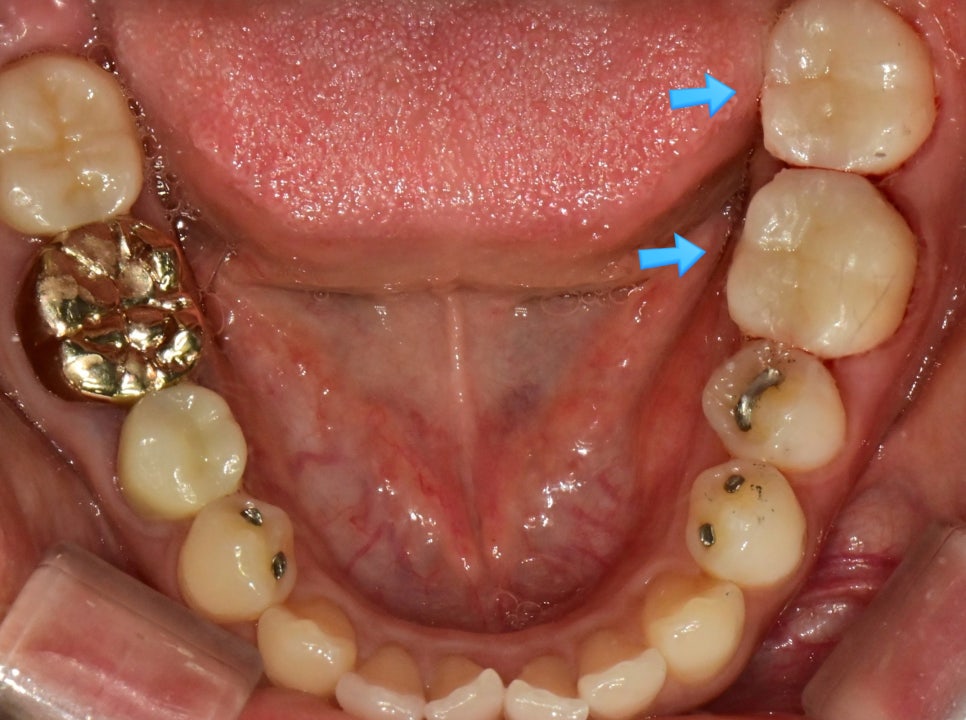

두 치아의 대형 아말감 — 변연 파절과 균열이 화살표로 표시된 임상 사진

▲ 아말감 팽창으로 인한 치아 크랙(균열) — 위 치아는 팽창으로 크랙, 아래 치아는 아말감 파절 후 이차 충치 진행

이러한 상태의 아말감은 재치료가 적합하며, 증상과 환자분의 의사에 따라 인레이 또는 크라운 치료를 진행합니다. 아말감의 크기가 넓은 경우에는 인레이보다 크라운 치료가 더 적절한 선택입니다.